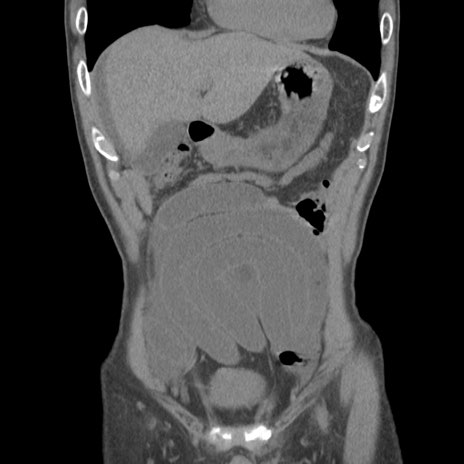

症例56 CT(冠状断像)

横断像